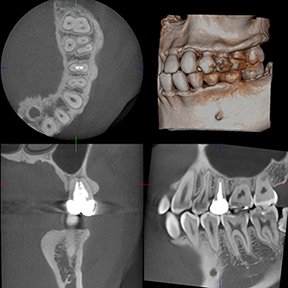

The Morita Accuitomo CT Scanner

Morita’s Most Advanced CBCT Unit

The Accuitomo CT scanner is Morita’s most advanced unit. Highly refined, it is the 4th generation of the Accuitomo product line. It offers a voxel size of just 80 µm and displays even the most subtle details of bone structure. This super-fine voxel combined with the unit’s 14 bit grayscale capability creates a wide dynamic range which produces the highest quality visualization of both hard and soft tissue areas.